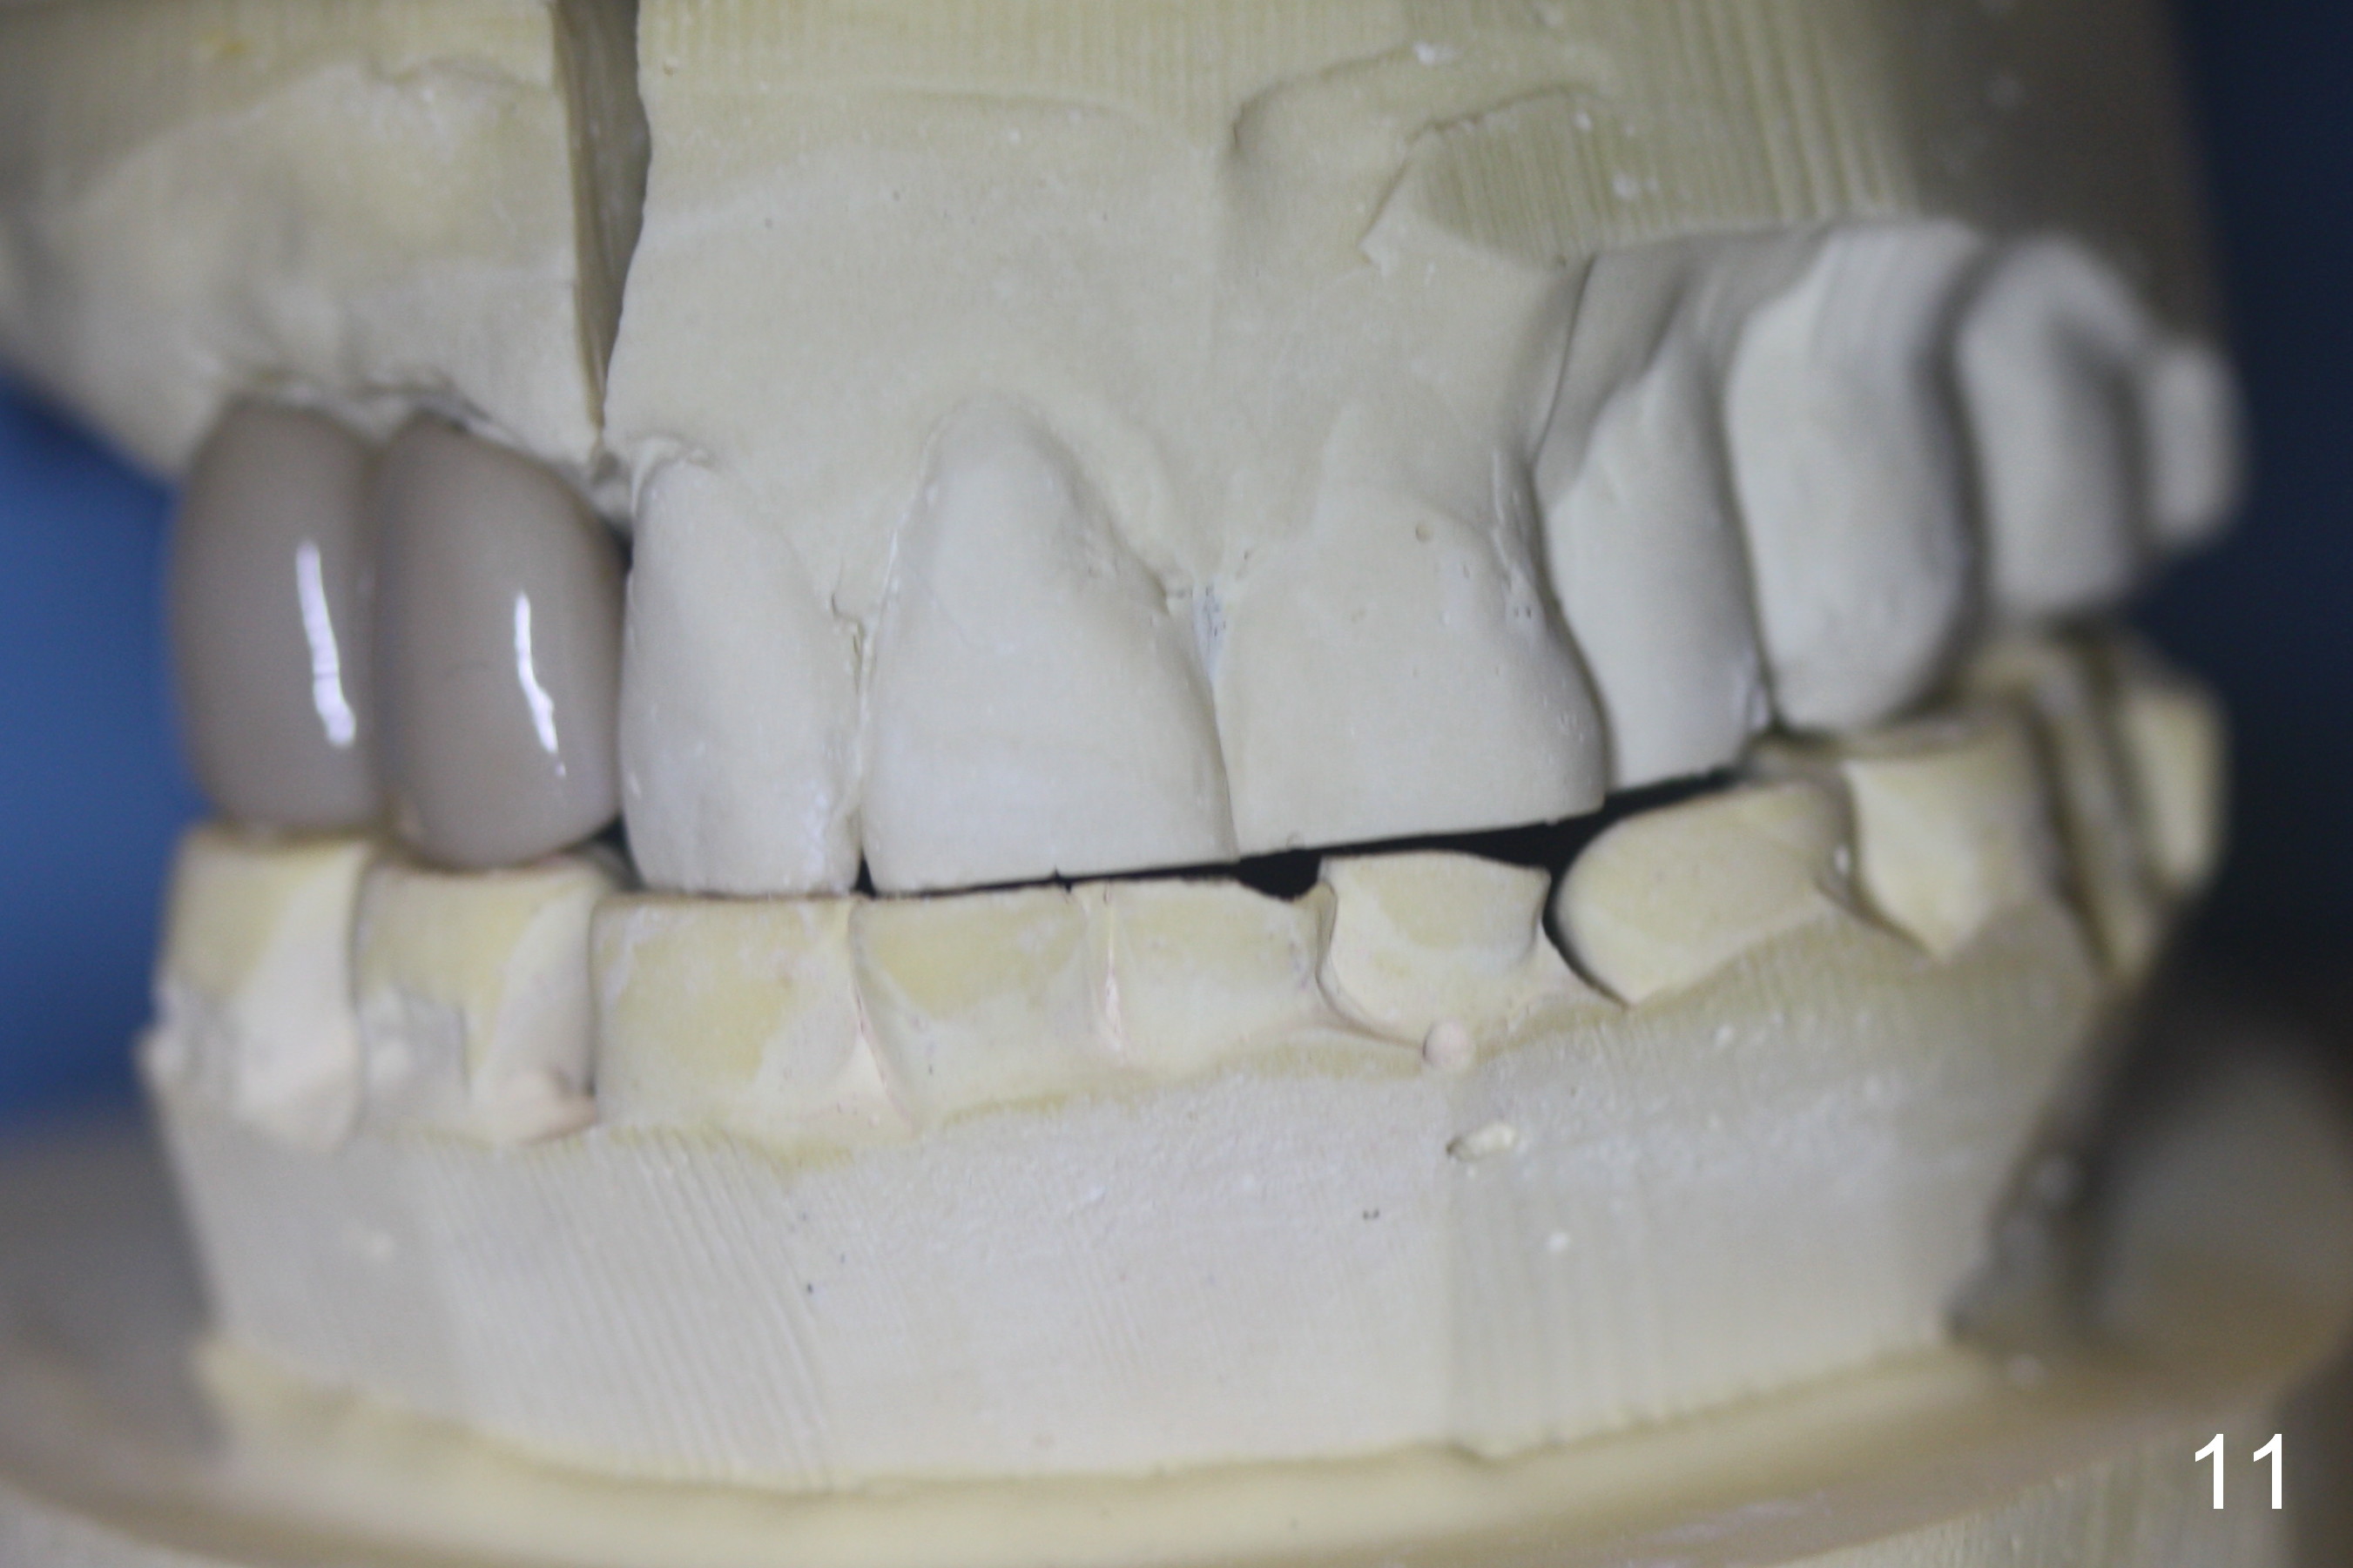

Several of CK's upper teeth (apparently in cross bite) are to be restored with implants (Fig.1). The first two are #5 and 6; note the oval roots (Fig.2). After extraction, and curettage, osteotomy starts in the palatal aspect of each socket. The 1st intraop PA shows that the trajectory at #6 is incorrect (Fig.3). After adjustment, osteotomies look parallel (Fig.4: D: 3.5x20 mm drill; T: 4.5x20 mm tap). This suggests how important it is to use parallel pins to check initial osteotomies for neighboring implants (Fig.3). The trajectory of the implants remains acceptable (Fig.5: 4.5x20 mm with insertion torque »60 Ncm); so is the position of the implants (as palatal as possible; Fig.6 (*: bone graft)). Immediate provisionals are fabricated in cross bite.

Bone density in the distal gap of #5 appears to have increased 3 months postop (Fig.7). Prior to definitive restoration cementation (3.5 months postop), the buccal plate does not collapse (Fig.8). There is no occlusal contact of the new restorations (Fig.9 *), probably due to bite discrepancy (Fig.10,11).